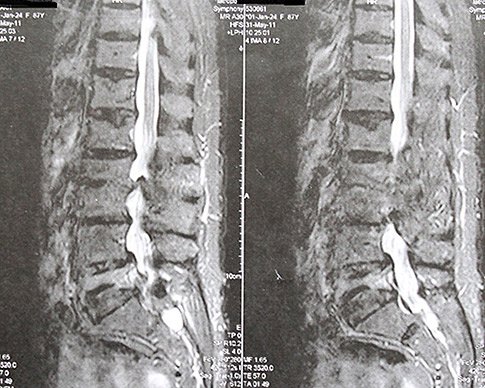

Φωτό 2: Αντιθέτως, εδώ βλέπουμε την εικόνα μιας ηλικιωμένης γυναίκας άνω των 90 ετών με εκτεταμένες δομικές βλάβες, όπως συμπιεστικά κατάγματα λόγω οστεοπόρωσης αλλά και σημαντική σπονδυλική στένωση σε πολλά επίπεδα, η οποία δεν παραπονείται για πόνους. Χρειάζεται λοιπόν ένας άλλος τρόπος προσέγγισης των μυοσκελετικών προβλημάτων, ο οποίος να είναι επιστημονικά επαρκώς τεκμηριωμένος, να δίνει την πραγματική εικόνα και να μη δημιουργεί λανθασμένες αντιλήψεις και φοβίες στον πληθυσμό, οι οποίες δημιουργούν χρονίως πάσχοντες ανθρώπους.